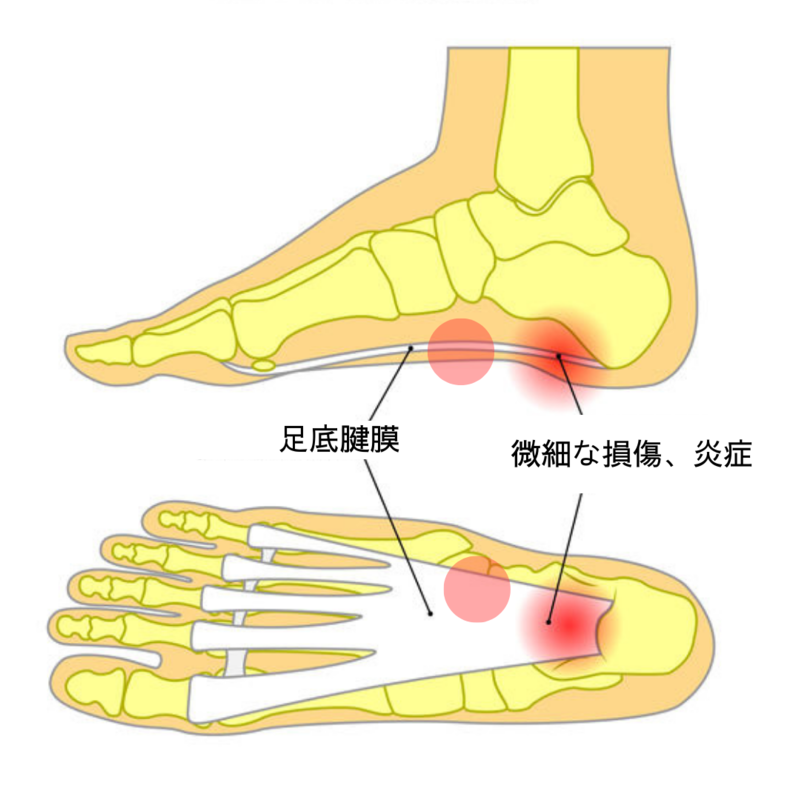

足底腱膜 足底腱膜炎とは

足底腱膜は踵(かかと)の骨から足の指へ広がる強靭な腱の膜です。足の土踏まず(縦アーチ)を支える重要な役割があります。

歩行・ランニングなどの荷重時に地面と足部の衝撃を和らげるクッションのような役割をします。

アーチ構造が崩れると、足底腱膜にさらなるストレスが加わります。そうなると、足底腱膜に微細な損傷や炎症が起こり、足の裏の痛みが出てくる場合があります。

足部の形状も重要です。扁平足やハイアーチ(甲高足)に症状が起きやすいとされています。